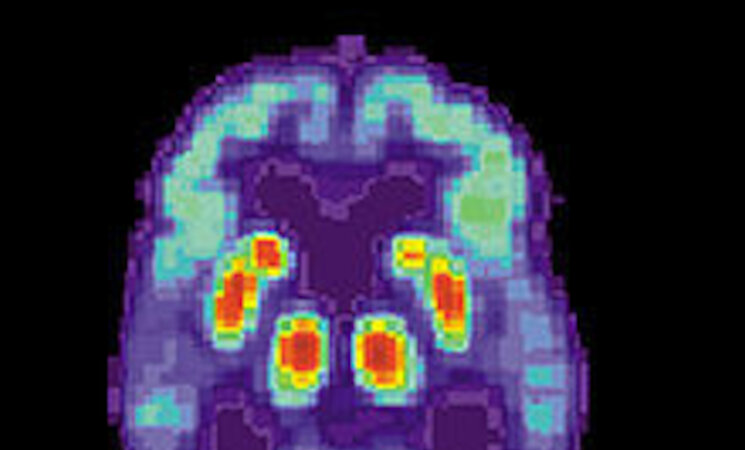

La Asociación Extremeña de Familiares de Personas con Alzheimer y otras enfermedades afines (Afaex) ha organizado una serie de actividades con motivo del Día Mundial de esta patología el próximo 21 de septiembre, bajo el lema "Sigo siendo yo".